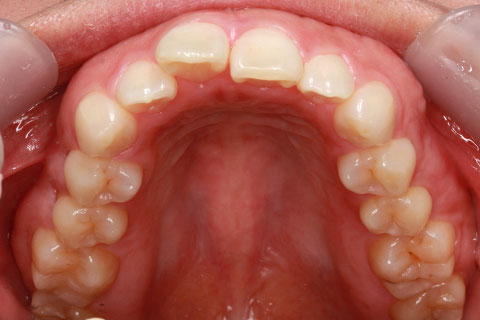

ハーフリンガル矯正3(上の歯のみ舌側矯正で治療)

治療前

治療中(開始直後)

治療中(開始半年後)

治療後

- 年齢・性別

- 25歳女性

- 治療期間

- 2年0ヶ月

- 抜歯

- 上下4番抜歯

- 治療費

- 110万円

- 備考

- 治療内容

- 施術の副作用(リスク)

- 表側矯正と比較して、力学的な操作性が複雑なため、ボーイングエフェクトを起こしやすい。